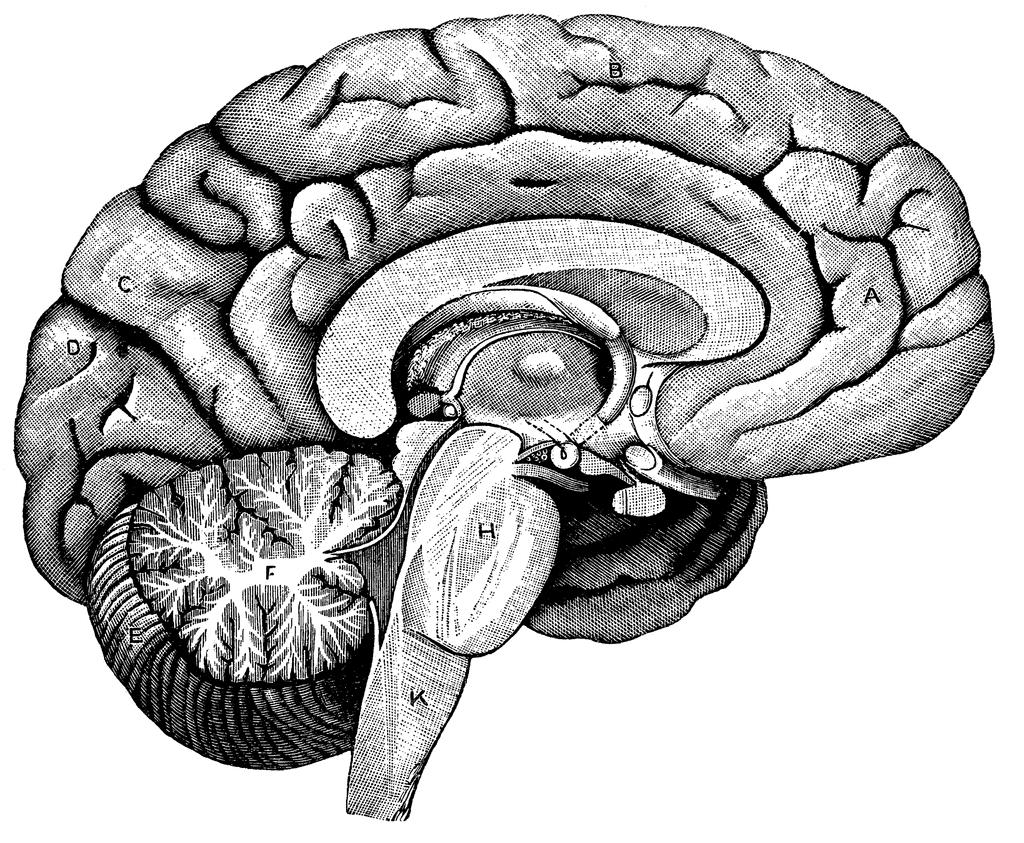

Understanding The Empty Brain Diagram: A Comprehensive Analysis

techschems.comHuman Brain Diagram Blank

techschems.comHuman Brain Diagram Blank

Human Brain Diagram Blank

Blank Brain Diagram

ar.inspiredpencil.comBlank Diagram Of The Inside Of The Brain Blank Brain Diagram System

ar.inspiredpencil.comBlank Diagram Of The Inside Of The Brain Blank Brain Diagram System

www.pinterest.combrain anatomy diagram blank drawing coloring human inside system choose board